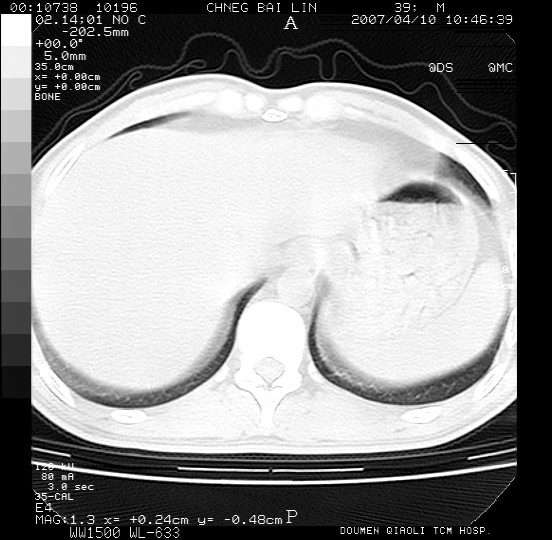

男,39岁。10天前自觉感冒,曾输液一次内容不详曾有吸毒史。现有咳嗽、咳痰胸闷。

两肺弥漫分布的网状毛玻璃状阴影,边缘模糊不清,纵隔未见明显淋巴结肿大

诊断:机遇性肺部感染